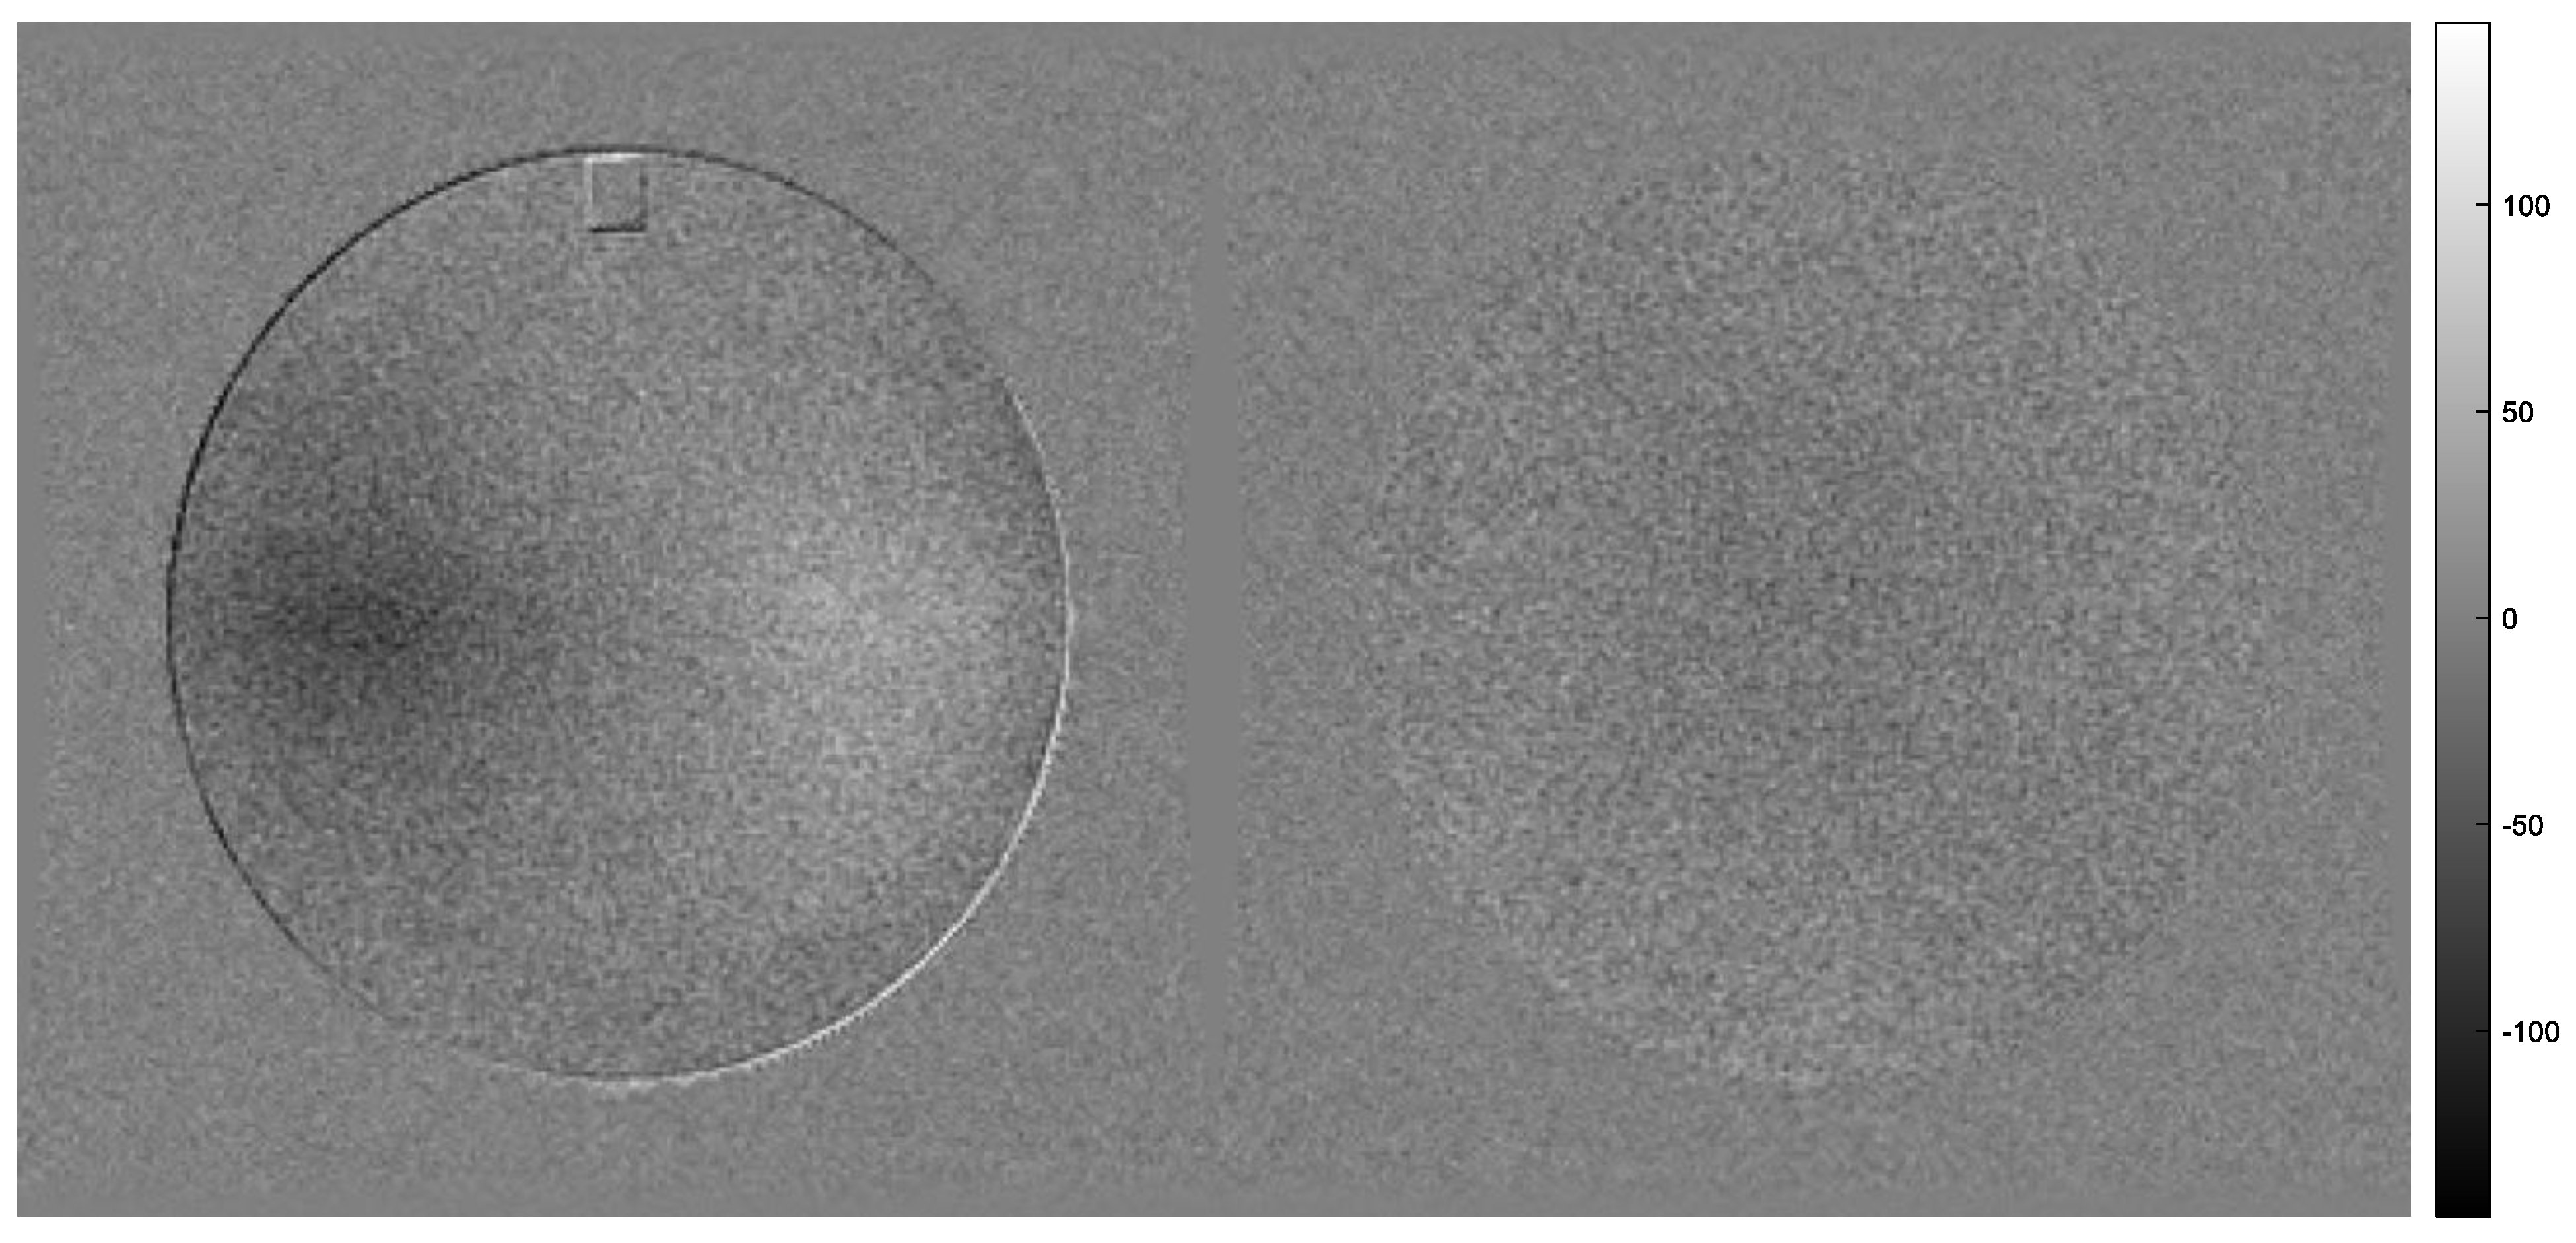

- The SNR is calculated by Equation (6), where is the average value of the main circular ROIs (UFOV) of slices #7 (), #6 ( or the average of the two , and σD is the standard deviation of the signal intensity of the UFOV of the image produced when subtracting one image from another [2]. In other words, the SNR can be calculated in any of the following ways:

- Another variation of the above SNR definitions can be derived, using the subtraction of slice #7 between two identical sequence scans acquired within 5 min or less (already referred to as series A and B, respectively). The concept of two image subtraction is described in the NEMA document [20] and can be applied to images from different acquisitions, provided that 5 min or less have elapsed between the two. Following this concept, Equations (11)–(13) can be used, with the only difference being that the subscripts 1 and 2 are used to describe the signal and noise in slice #7 of the first (series A) and the second acquisition (series B), respectively.